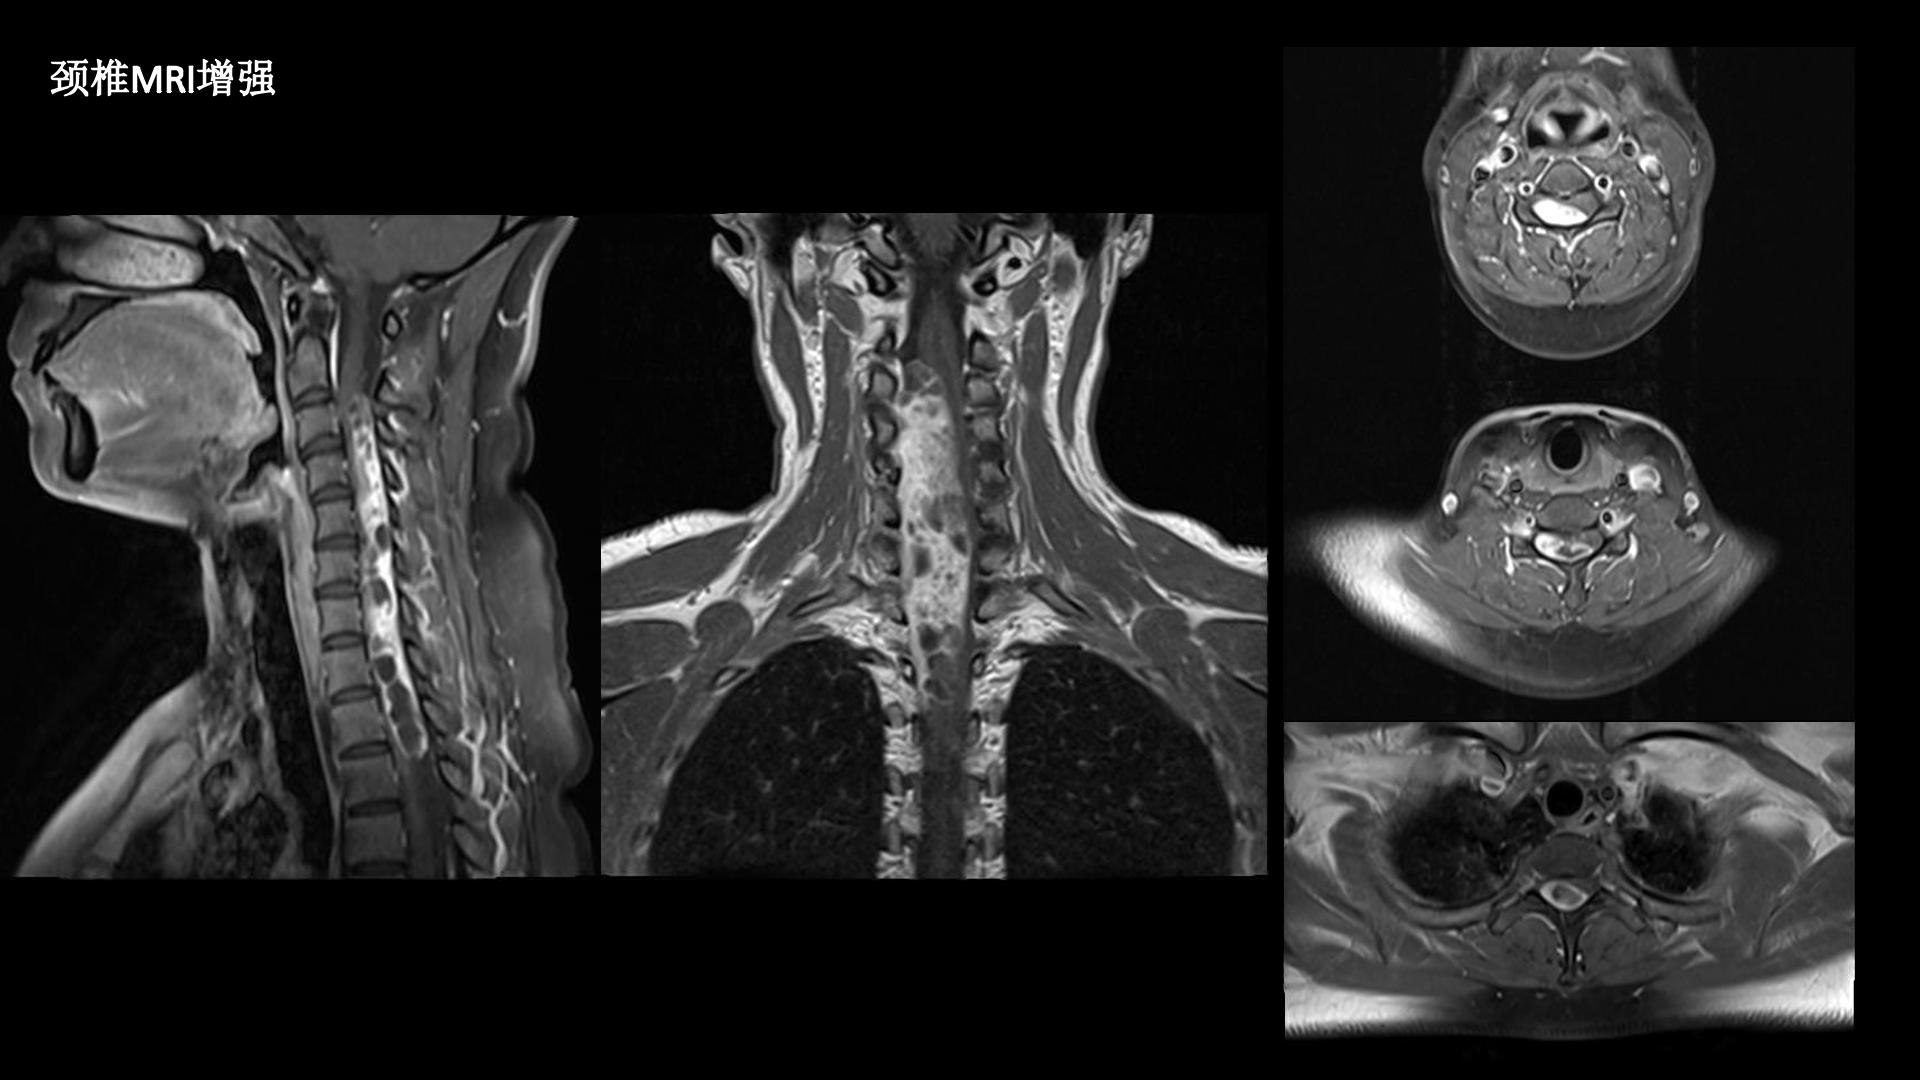

西安交通大学第二附属医院刘重霄教授团队:一例巨长型颈胸椎神经鞘瘤切除术+脊柱内固定术